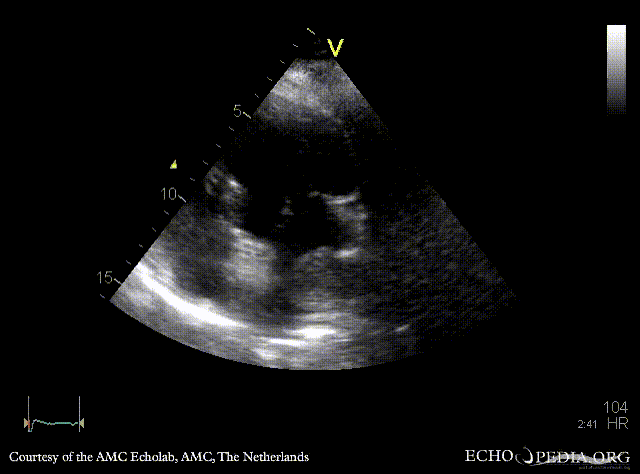

| Courtesy of: AMC Echolab, AMC, The Netherlands | |

| PSAX: tumor mass in left atrium | A4CH |